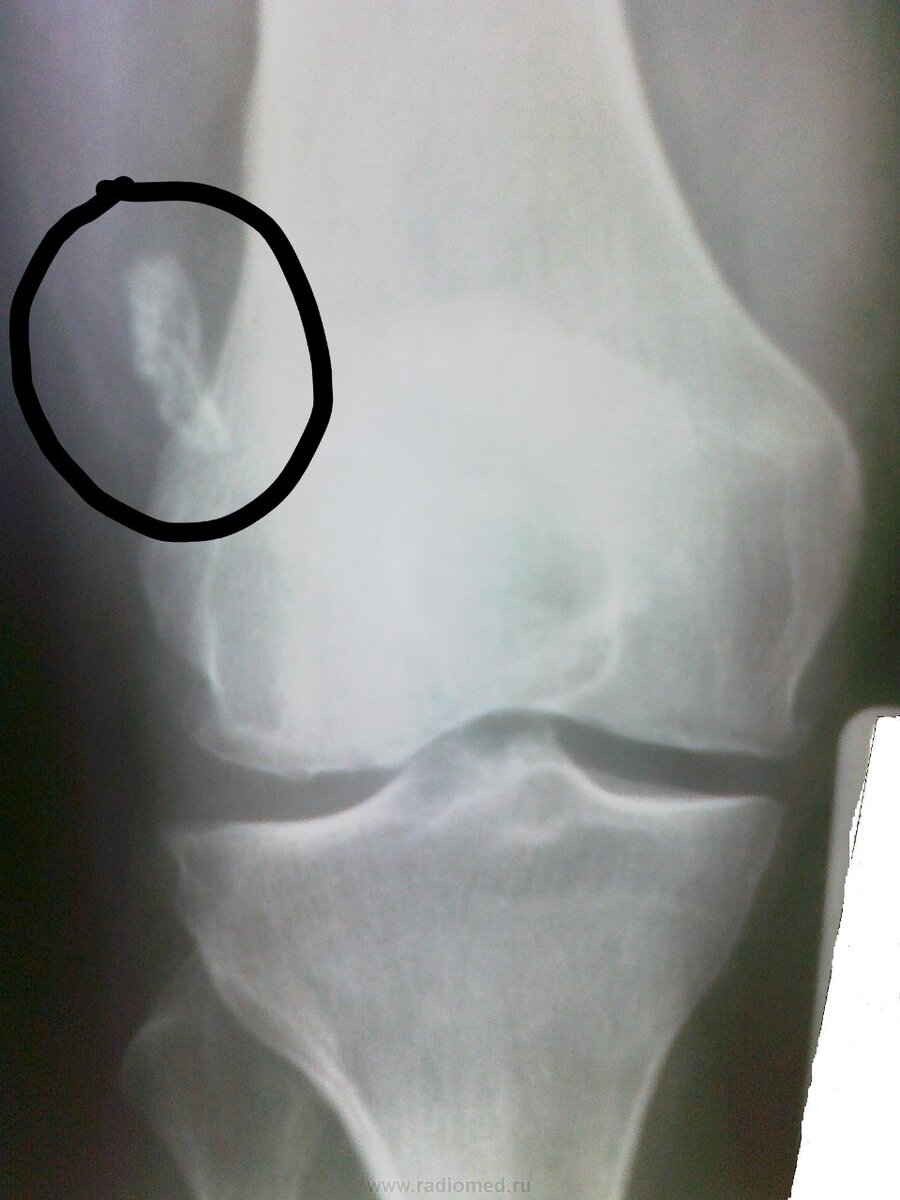

Сегодня разберем такую болезнь, как хондроматоз. ⠀ Хондроматоз – это диспластический процесс, сопровождающийся формированием хрящевых (хондромных) тел в синовиальной оболочке суставов. ⠀

Если говорить просто, в суставе появляются от одного до сотни и более плотных округлых тел. Они мешают работе сустава, вызывают боли, хруст, блокады сустава. Причина их появления до конца не известна. Есть хондроматоз врожденный, когда дети уже рождаются с хондромными телами в суставе, а есть приобретенный, чаще из-за каких-либо травм сустава. ⠀ Лечение только оперативное, открытое или эндоскопическое удаление хондромных тел из сустава.

Если это не сделать, то хондромные тела неизбежно разрушат хрящевую ткань, что приведет к артрозу и замене сустава! ⠀ Если есть вышеописанные симптомы, не откладывайте, делайте МРТ и приходите на консультацию)